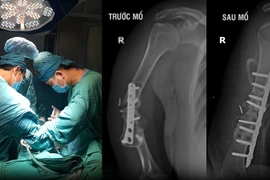

Các bác sĩ Bệnh viện Bãi Cháy đã phẫu thuật thành công mở cân cơ, thay thế động mạch cánh tay, động mạch trụ, quay dập nát bằng tĩnh mạch hiển đảo chiều, phục hồi cân cơ bảo tồn cánh tay cho người bệnh bị tai nạn lao động.